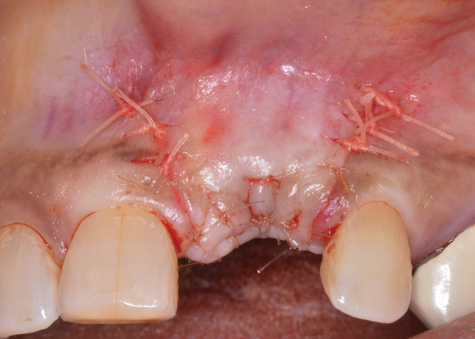

(18.) A subepithelial, connective tissue graft from the palate is affixed over the collagen bone scaffold and around the abutments of the three involved implants.

Figure 18

After gentle debridement with glycine air abrasion and sterile saline, a cross-linked, porcine collagen bone matrix (OSSIX® VOLUMAX; Datum Dental Ltd.) was placed over the buccal aspect of all three affected implants (Figure 17). Next, a subepithelial, connective tissue graft harvested from the right aspect of the patient's hard palate was affixed over the bone scaffold and exposed implants and abutments (Figure 18). And finally, a coronally advanced flap was sutured over the hard- and soft-tissue grafts. The 1-month, follow-up photograph demonstrates incomplete, but significant coverage of the previously exposed implants and abutments (Figure 19).